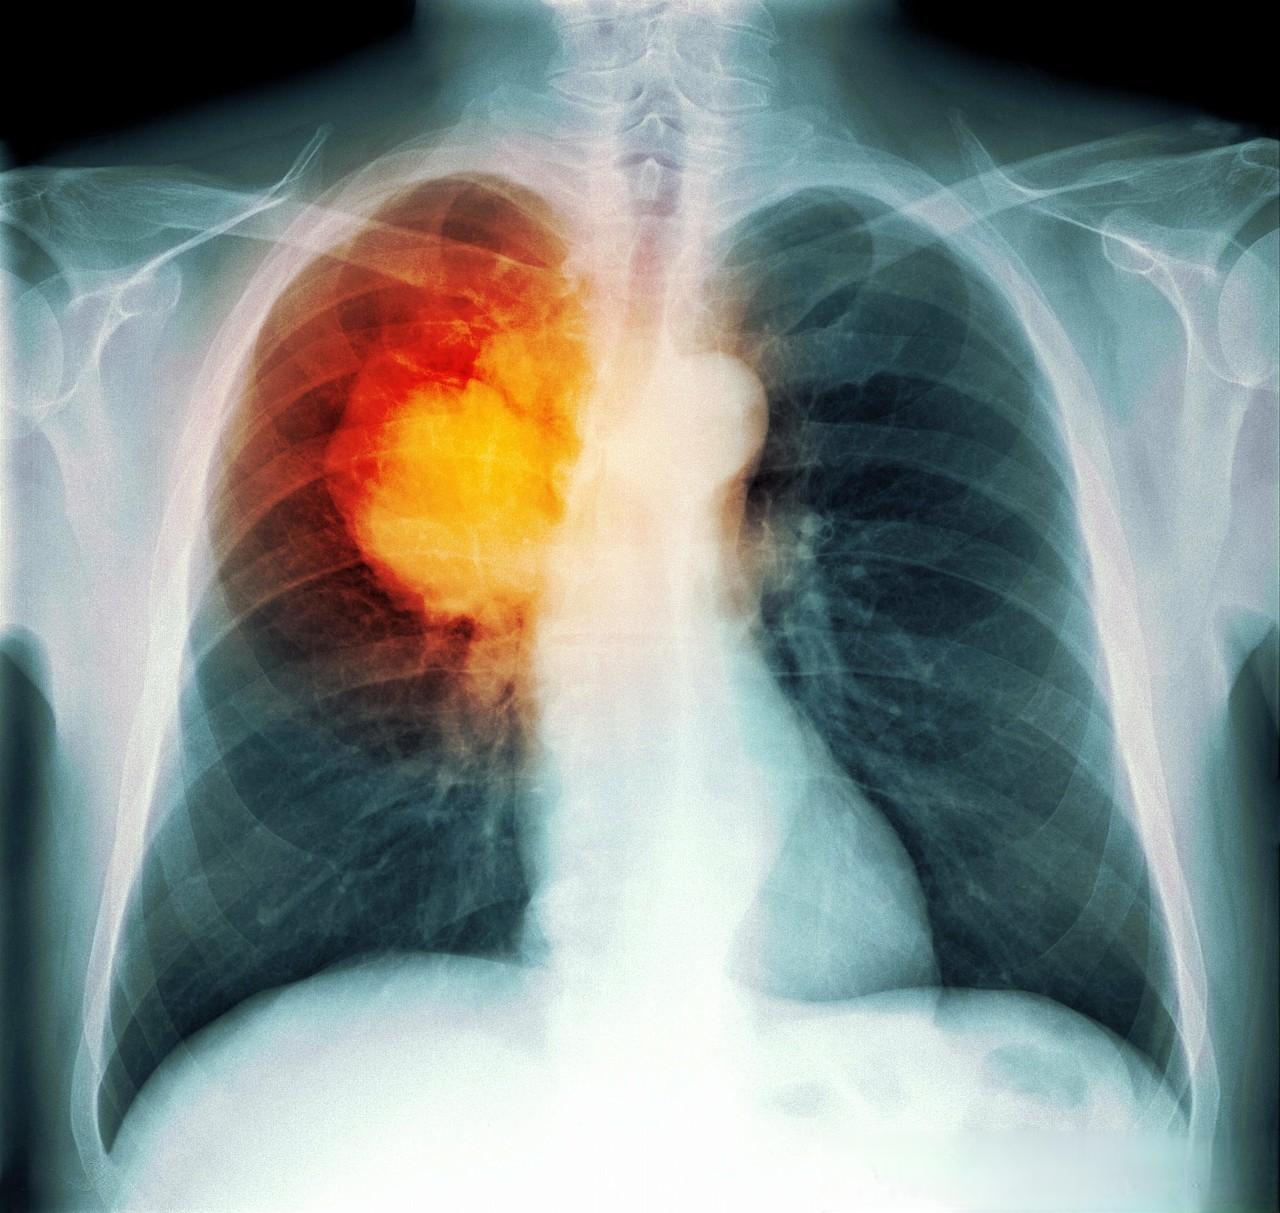

肺癌晚期患者常常面临一个棘手的问题 - 胸腔积液。据统计,约15%的肺癌患者在初次就诊时就已出现胸腔积液,而50%的肺癌患者在病程中会出现这一并发症。一旦出现胸腔积液,患者的中位生存时间仅为3~12个月。这种状况不仅严重影响患者的生活质量,还可能加速病情恶化。

胸腔积液的主要症状包括呼吸困难、胸痛和咳嗽。当积液量较大时,患者可能会感到明显的胸闷、气短,甚至影响日常生活。因此,及时有效的治疗对于缓解症状、提高生活质量至关重要。